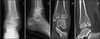

104

Pott’s # or Bimalleolar #

Where is the fracture located in a Pott’s # or Bimalleolar #

Fracture of the medial and lateral malleoli